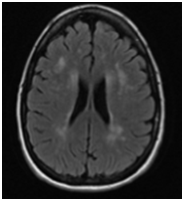

At 34 weeks of gestational age the patient was admitted to the hospital due to severe right eye pressure-like headache associated with transient right upper limb weakness for 24 hours. Her blood pressures were normal and preeclampsia was ruled out. The physical exam performed by the neurologist was significant for mild flattening of right nasolabial fold. There were no other abnormal neurologic or psychiatric findings. The MRI (Figure 1) showed multiple small foci of abnormal signal in the cerebral white matter consistent with micro vascular ischemic changes but no acute pathology. This episode was self-limited and the patient was discharged home in stable condition after 10 days.

• Figure 1 MRI performed at 34.0 weeks of gestation.

The most common lesions seen on MRI occur in the per ventricular and deep white matter. Lesions are initially nodular or punctiform and become diffuse and symmetric. The most suggestive areas affected by CADASIL are the external capsule and anterior temporal lobe. As opposed to multiple sclerosis, basal ganglia and thalamus are also affected. The severity is higher in symptomatic patients and increases dramatically with age.